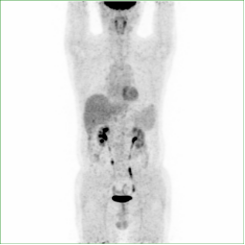

全身PET/CT显像正常图像: